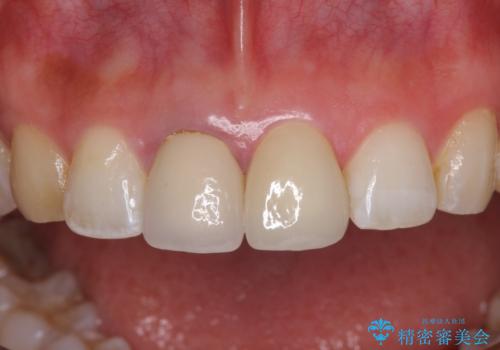

2本同時に処置をし、2本とも明るい色合いにすることをお勧めしましたが、今回は1歯のみとしました。

左右のバランスが取れ、患者様には大変満足していただきました。